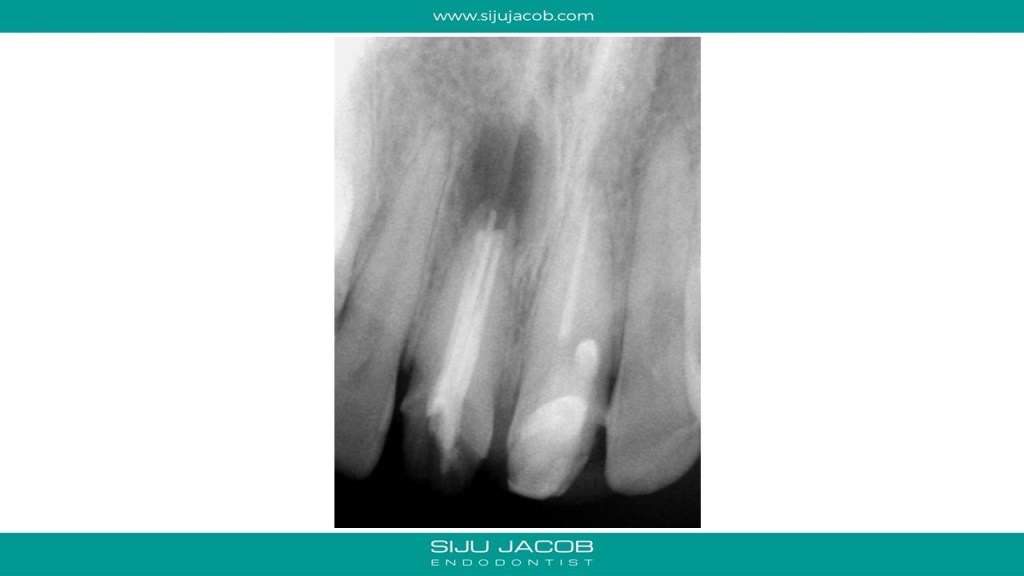

This was a patient who traveled from abroad from Treatment. We had only 9 days to do his treatment. So, we did endo and immediate surgery.